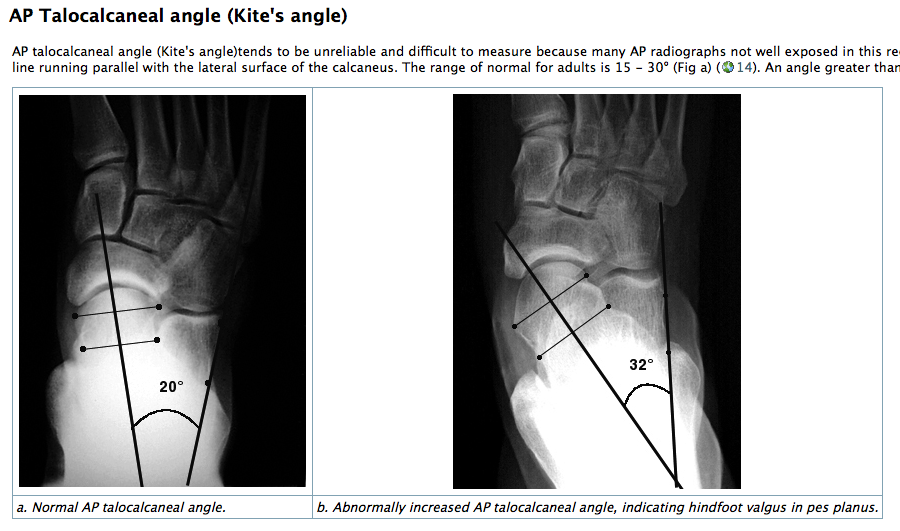

HINDFOOT VALGUS

• AP: Talo-calcaneal angle